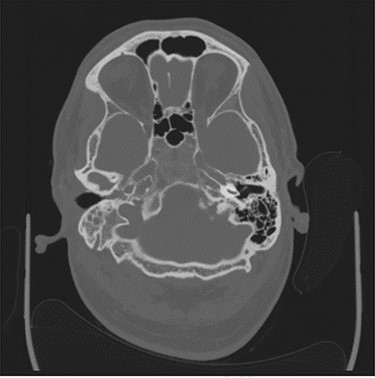

Computerized tomography (CT) of the internal meatuses demonstrated soft tissue thickening of the right middle ear cavity, aditus, antrum and mastoid air cells in keeping with otomastoiditis (Fig. 1), but no destructive or erosive pathology to account for the multiple neuropathies elicited on examination. A subsequent magnetic resonance imaging (MRI) scan demonstrated a 2.5 centimeter (cm) right skull base inflammatory mass, involving the internal carotid artery and jugular foramen (Fig. 2). Anti-microbial therapy was subsequently changed to intravenous meropenem and topical ciprofloxacin ear drops. The patient underwent a right cortical mastoidectomy and grommet insertion at Day 5, with well-pneumatized air cells and inflammatory tissue observed within the aditus.

Axial CT image slice showing opacification of the right middle ear cavity and mastoid air cells.